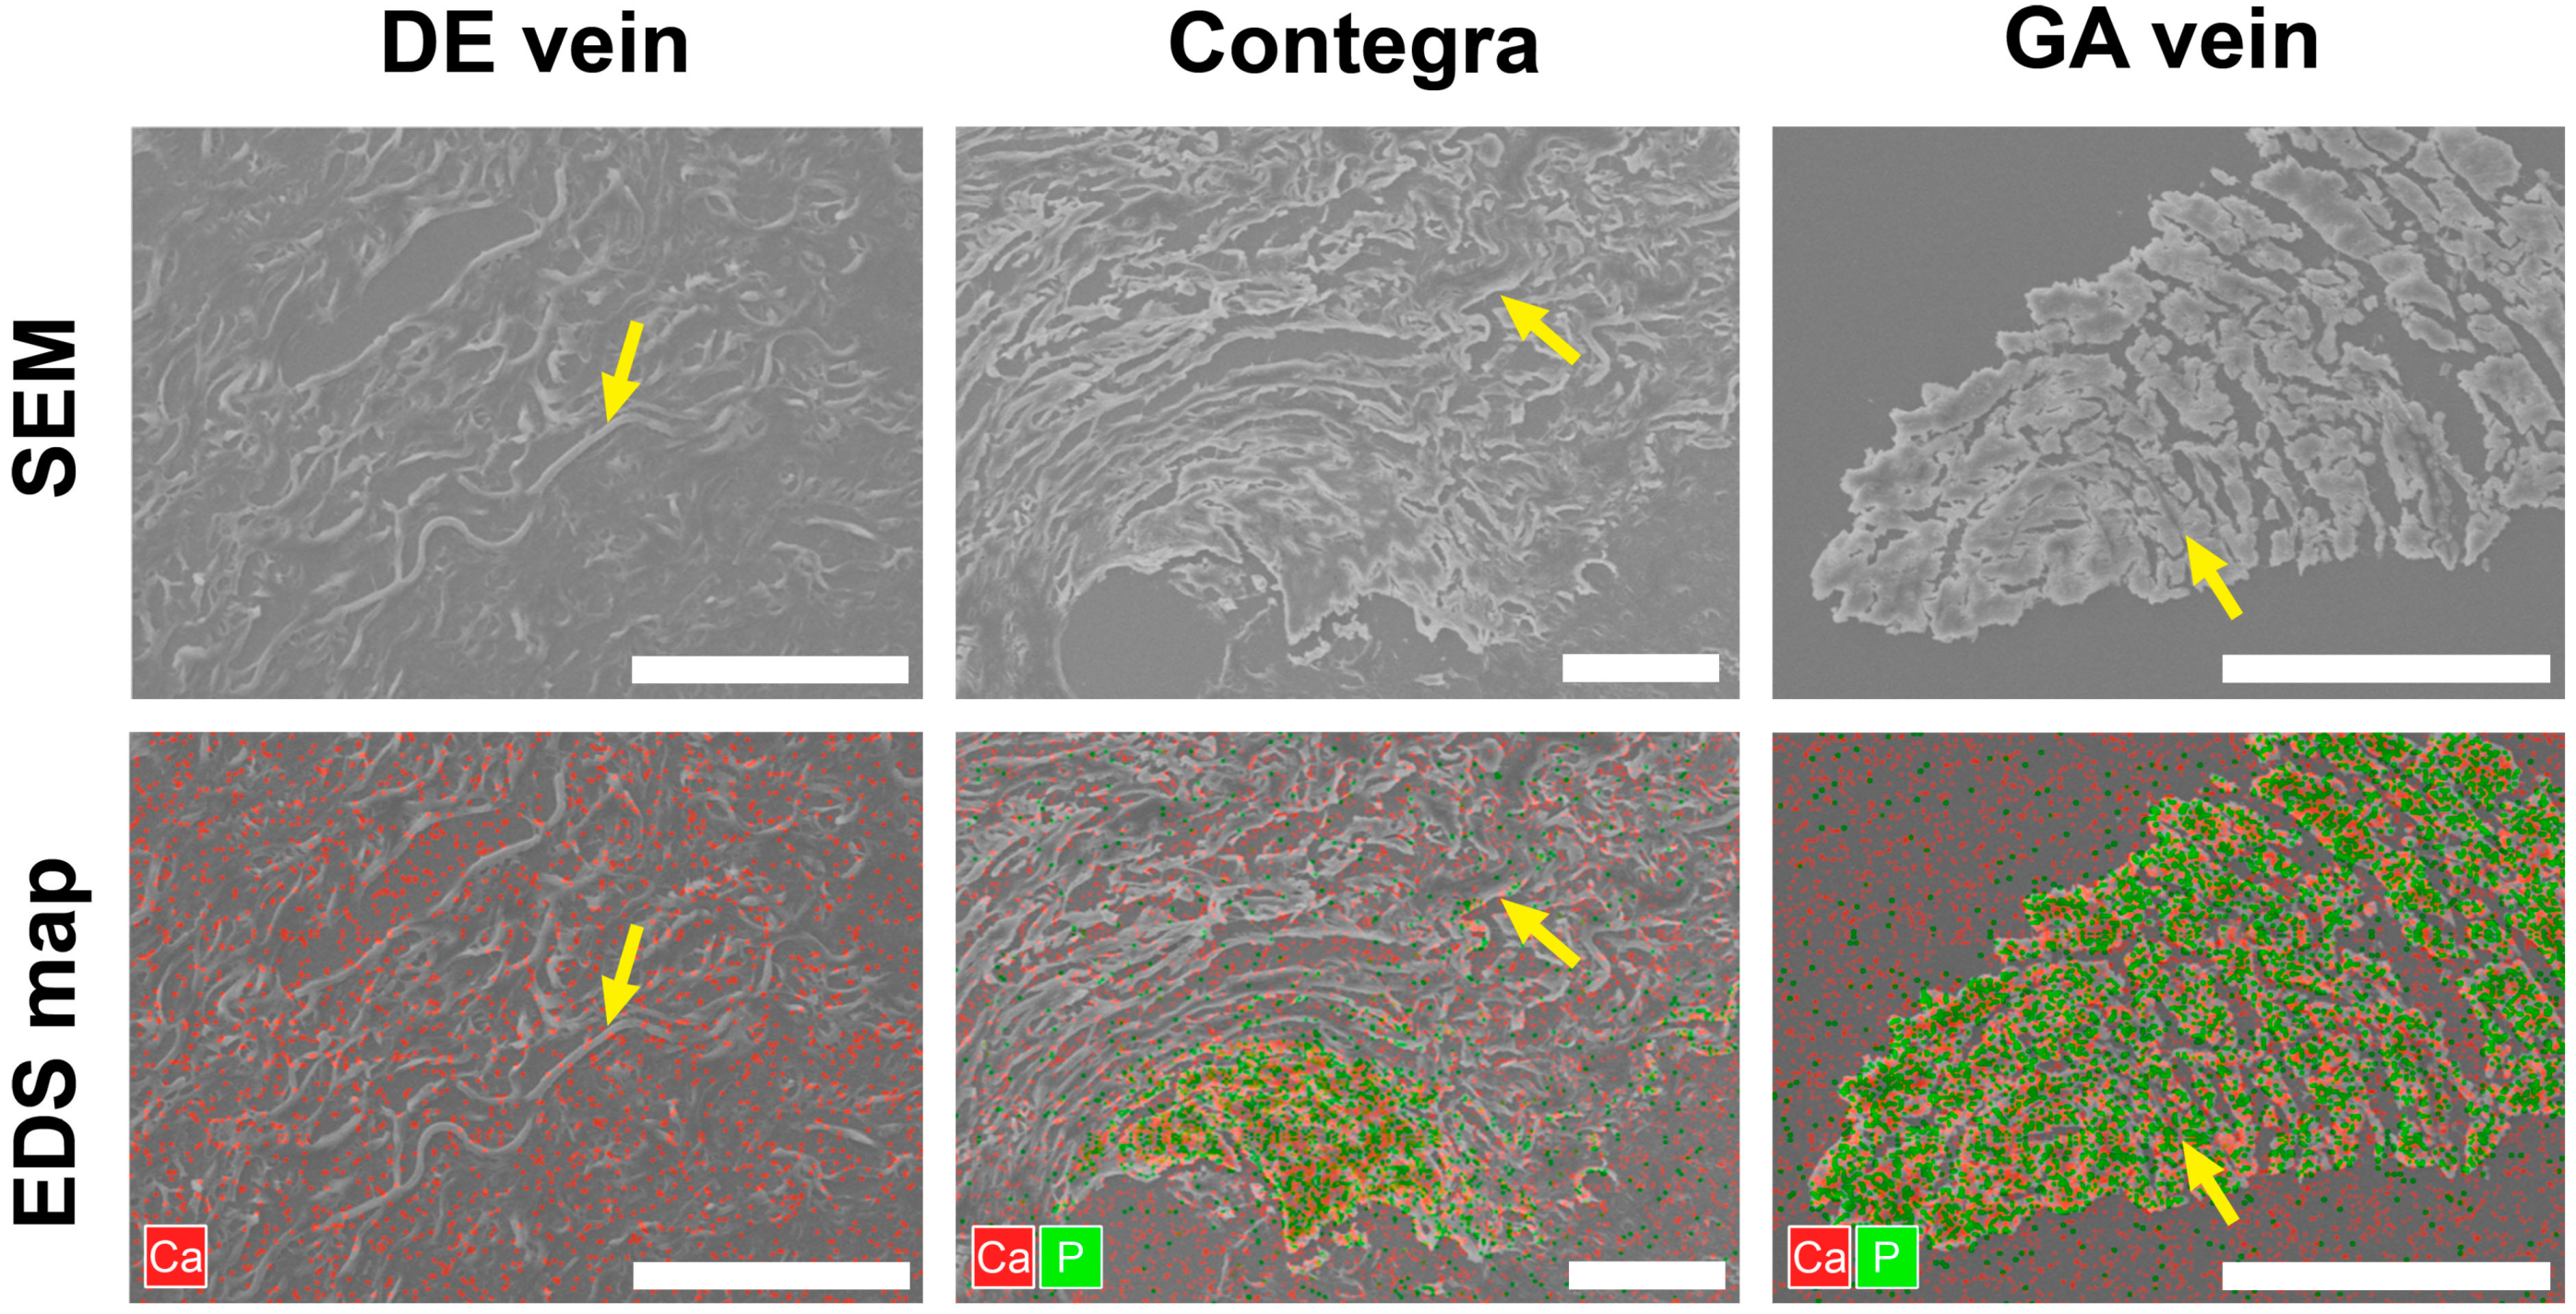

3.3. Scanning Electron Microscopy